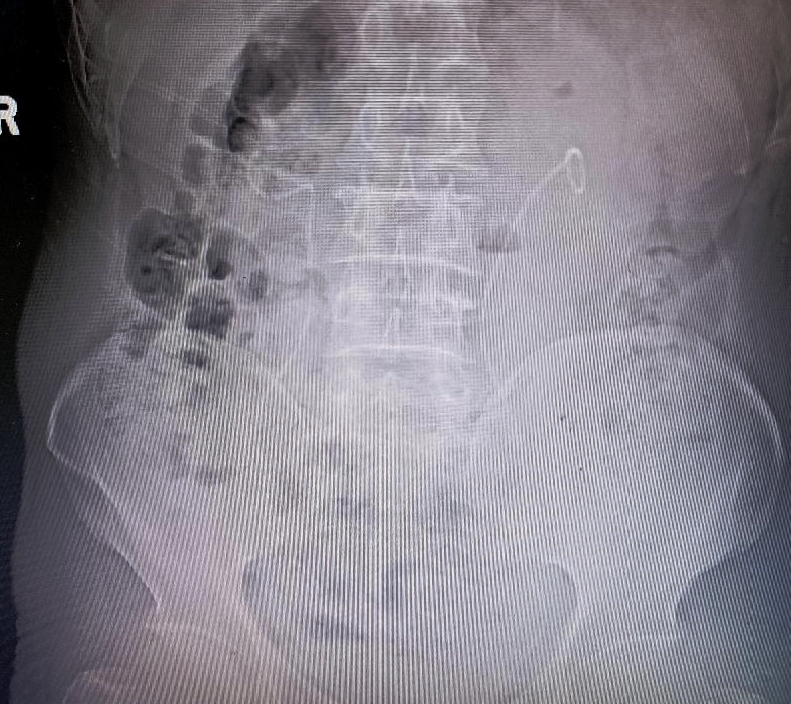

▼术后复查KUB,双侧肾结石取净